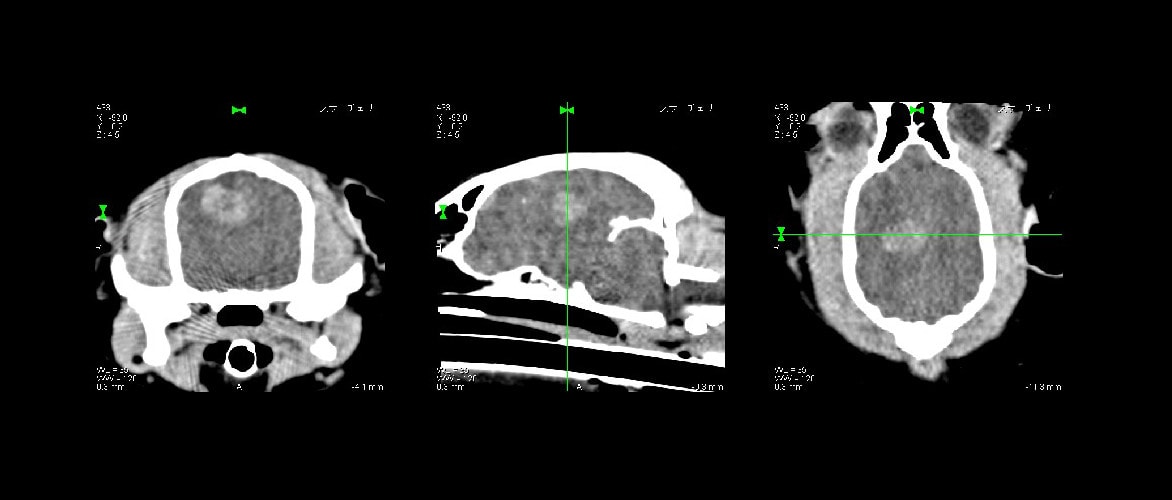

CT画像は冠状断面(輪切り)で見た断層画像です。CT撮影後その情報をコンピューター処理後、矢状断面に再構築した画像です。椎間板からの髄核物質が脊髄を圧迫しているのがよく分かります。CTで診断し、同時に手術することにより回復が早くなりました。